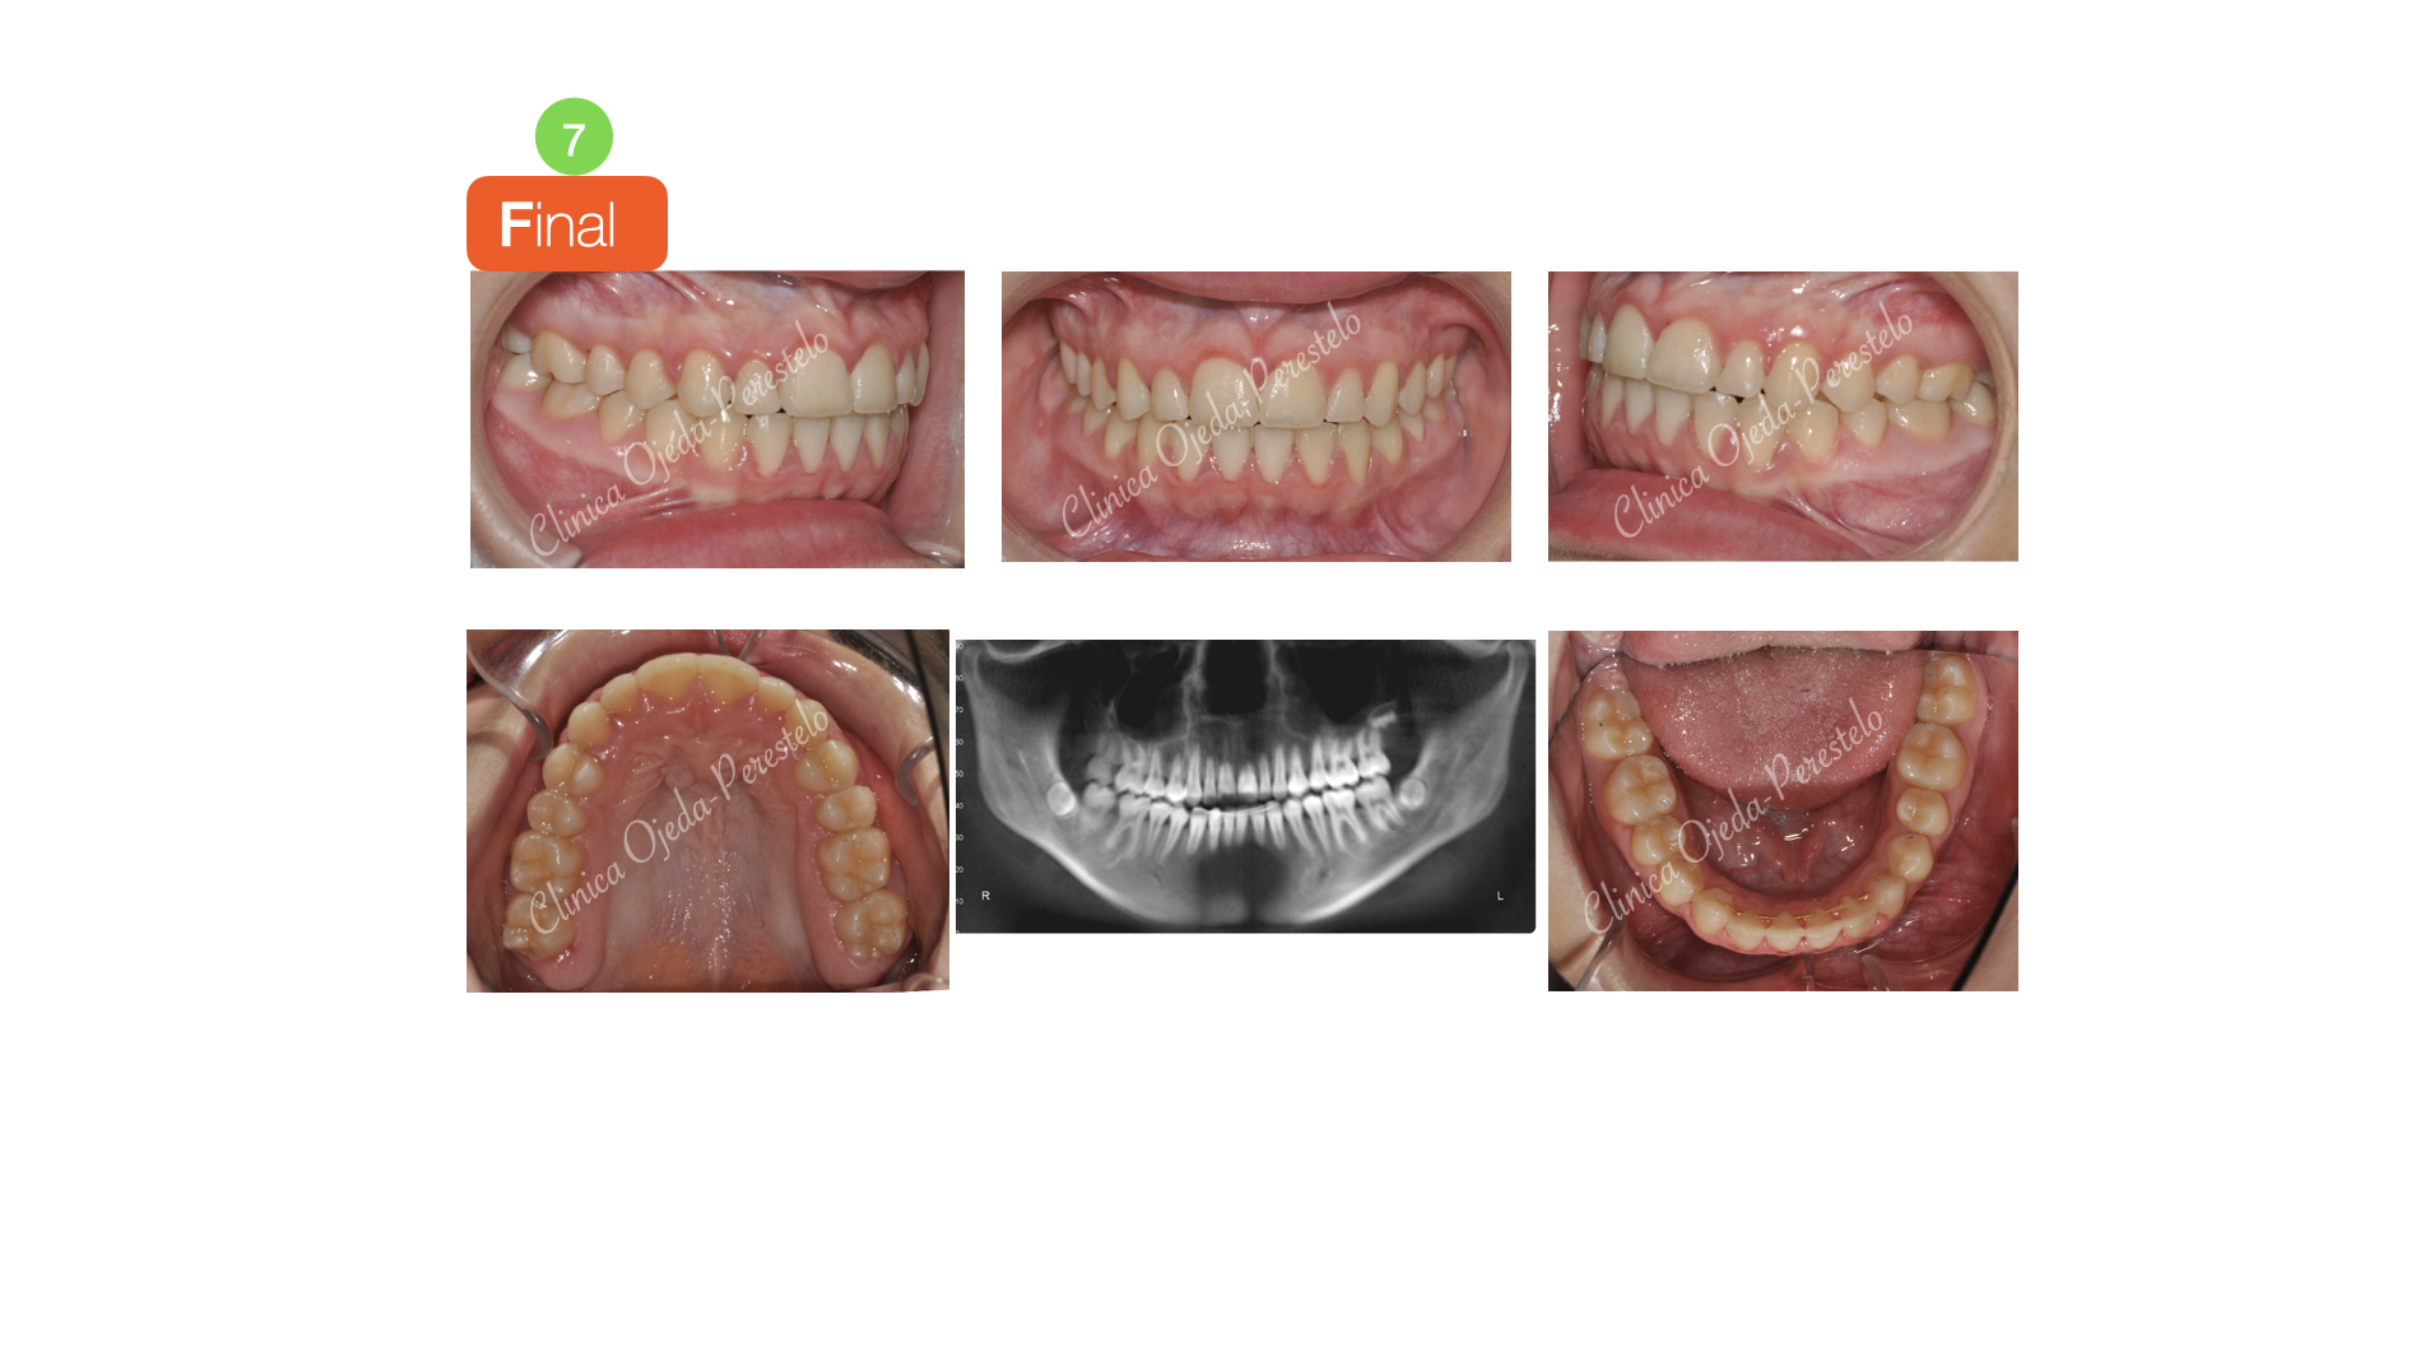

Clase III esquelética en dentición mixta

Paciente niña en dentición mixta y clase III esquelética tratado con Ortopedia Maxilar.

La paciente decidió continuar con una segunda fase de Ortodoncia fija a efectos de conseguir una correcta articulación dentaria y una adecuada estética de la sonrisa.

Quisieramos destacar la mejoría experimentada en la estética facial y dentaria .